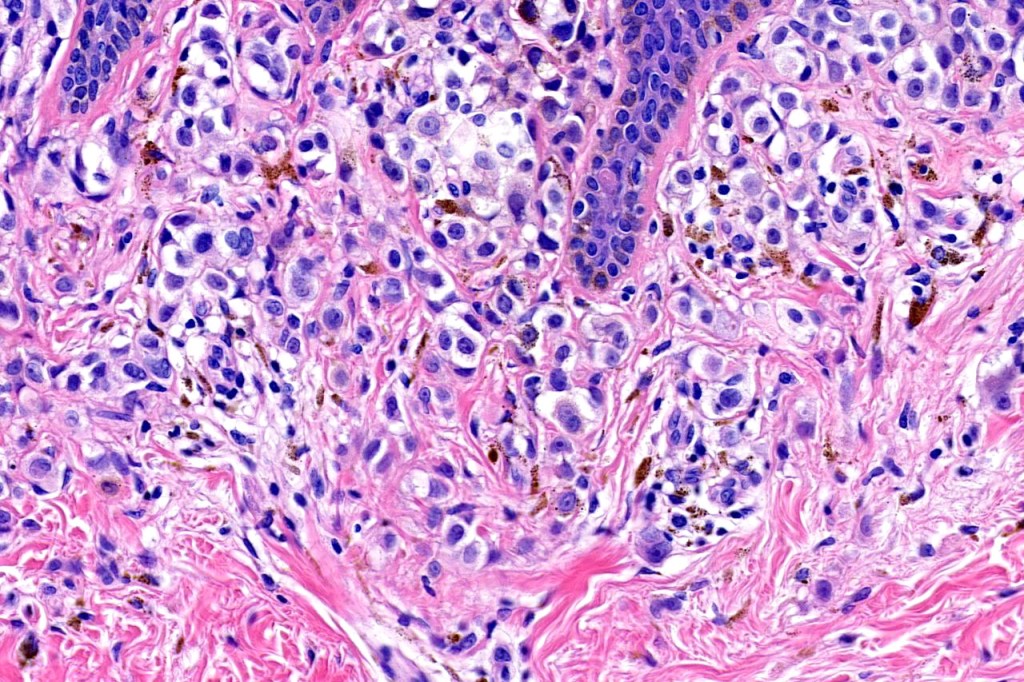

•Mimics type-A cells, (lesions which mimic type B nevus cells are often classified as small cell melanoma, this is important as the differential diagnosis is very different- see separate blog)

•Subtle or not so subtle impaired maturation with depth (sometimes this is evident at scanning magnification)

•Subtle nucleolar prominence

•Subtle pleomorphism

•Mitoses invariable including often in the deep aspect

•HMB45 expressed throughout